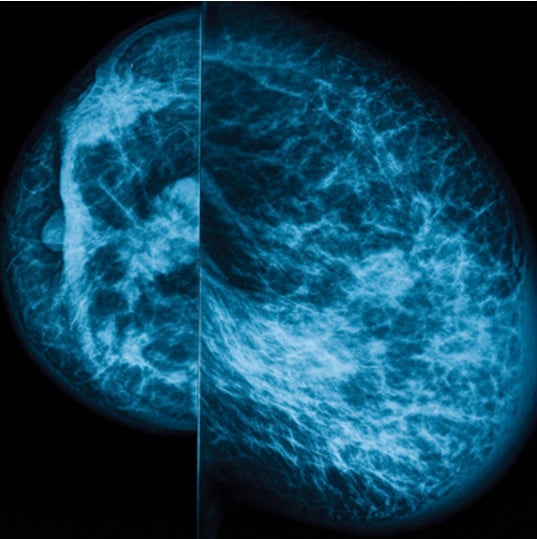

UCSF Breast Imaging delivers an expert overview of clinically relevant continuing medical education topics. Through didactic lectures, challenging case presentations, and faculty Q&A sessions, speakers highlight the latest developments, sharply focusing on the use of multimodality imaging and intervention (mammography, ultrasound and MRI).

- Develop a skillful, practical approach to mammography and breast US